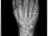

Röntgenbilder